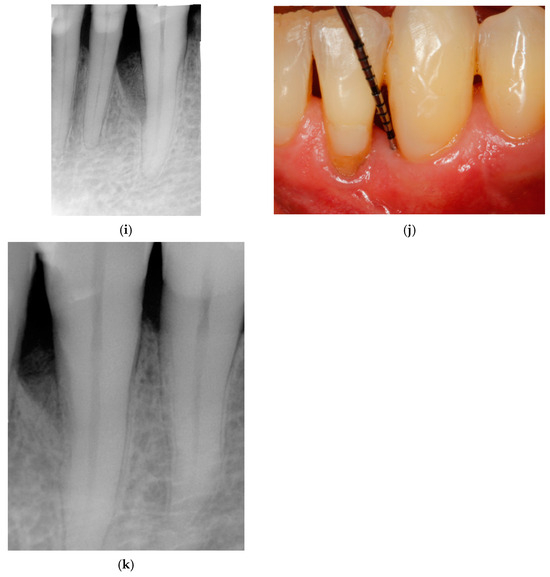

⚠裁断済み 乳頭再建 = Papilla reconstruction Entire Papilla Preservation Technique with Enamel Matrixの詳細情報

Entire Papilla Preservation Technique with Enamel Matrix。fonc-11-718946-g001.jpg。Interimplant papilla reconstruction at second-stage surgery。裁断しています。Interdental Papilla Reconstruction - クインテッセンス出版。「乳頭再建 = Papilla reconstruction」山口文誉 / 鈴木真名 / 髙橋雅仁定価: ¥ 14000#山口文誉 #鈴木真名 #髙橋雅仁 #本 #自然/医療・薬学・健康